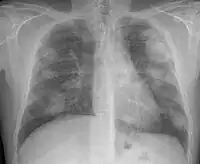

There are three key elements to the diagnosis of silicosis. First, the patient history should reveal exposure to sufficient silica dust to cause this illness. Second, chest imaging (usually chest x-ray) that reveals findings consistent with silicosis. Third, there are no underlying illnesses that are more likely to be causing the abnormalities. Physical examination is usually unremarkable unless there is complicated disease. The examination findings are not specific for silicosis.[19]

For uncomplicated silicosis, chest x-ray will confirm the presence of small (< 10 mm) nodules in the lungs, especially in the upper lung zones. Using the ILO classification system, these are of profusion 1/0 or greater and shape/size "p", "q", or "r". Lung zone involvement and profusion increases with disease progression. In advanced cases of silicosis, large opacity (> 1 cm) occurs from coalescence of small opacities, particularly in the upper lung zones.

With retraction of the lung tissue, there is compensatory emphysema. Enlargement of the hilum is common with chronic and accelerated silicosis. In about 5–10% of cases, the nodes will calcify circumferentially, producing so-called "eggshell" calcification. This finding is not pathognomonic (diagnostic) of silicosis. In some cases, the pulmonary nodules may also become calcified.

Chronic simple silicosis

Usually resulting from long-term exposure (10 years or more) to relatively low concentrations of silica dust and usually appearing 10–30 years after first exposure.[22] This is the most common type of silicosis. Patients with this type of silicosis, especially early on, may not have obvious signs or symptoms of disease, but abnormalities may be detected by x-ray. Chronic cough and exertional dyspnea (shortness of breath) are common findings. Radiographically, chronic simple silicosis reveals a profusion of small (<10 mm in diameter) opacities, typically rounded, and predominating in the upper lung zones.